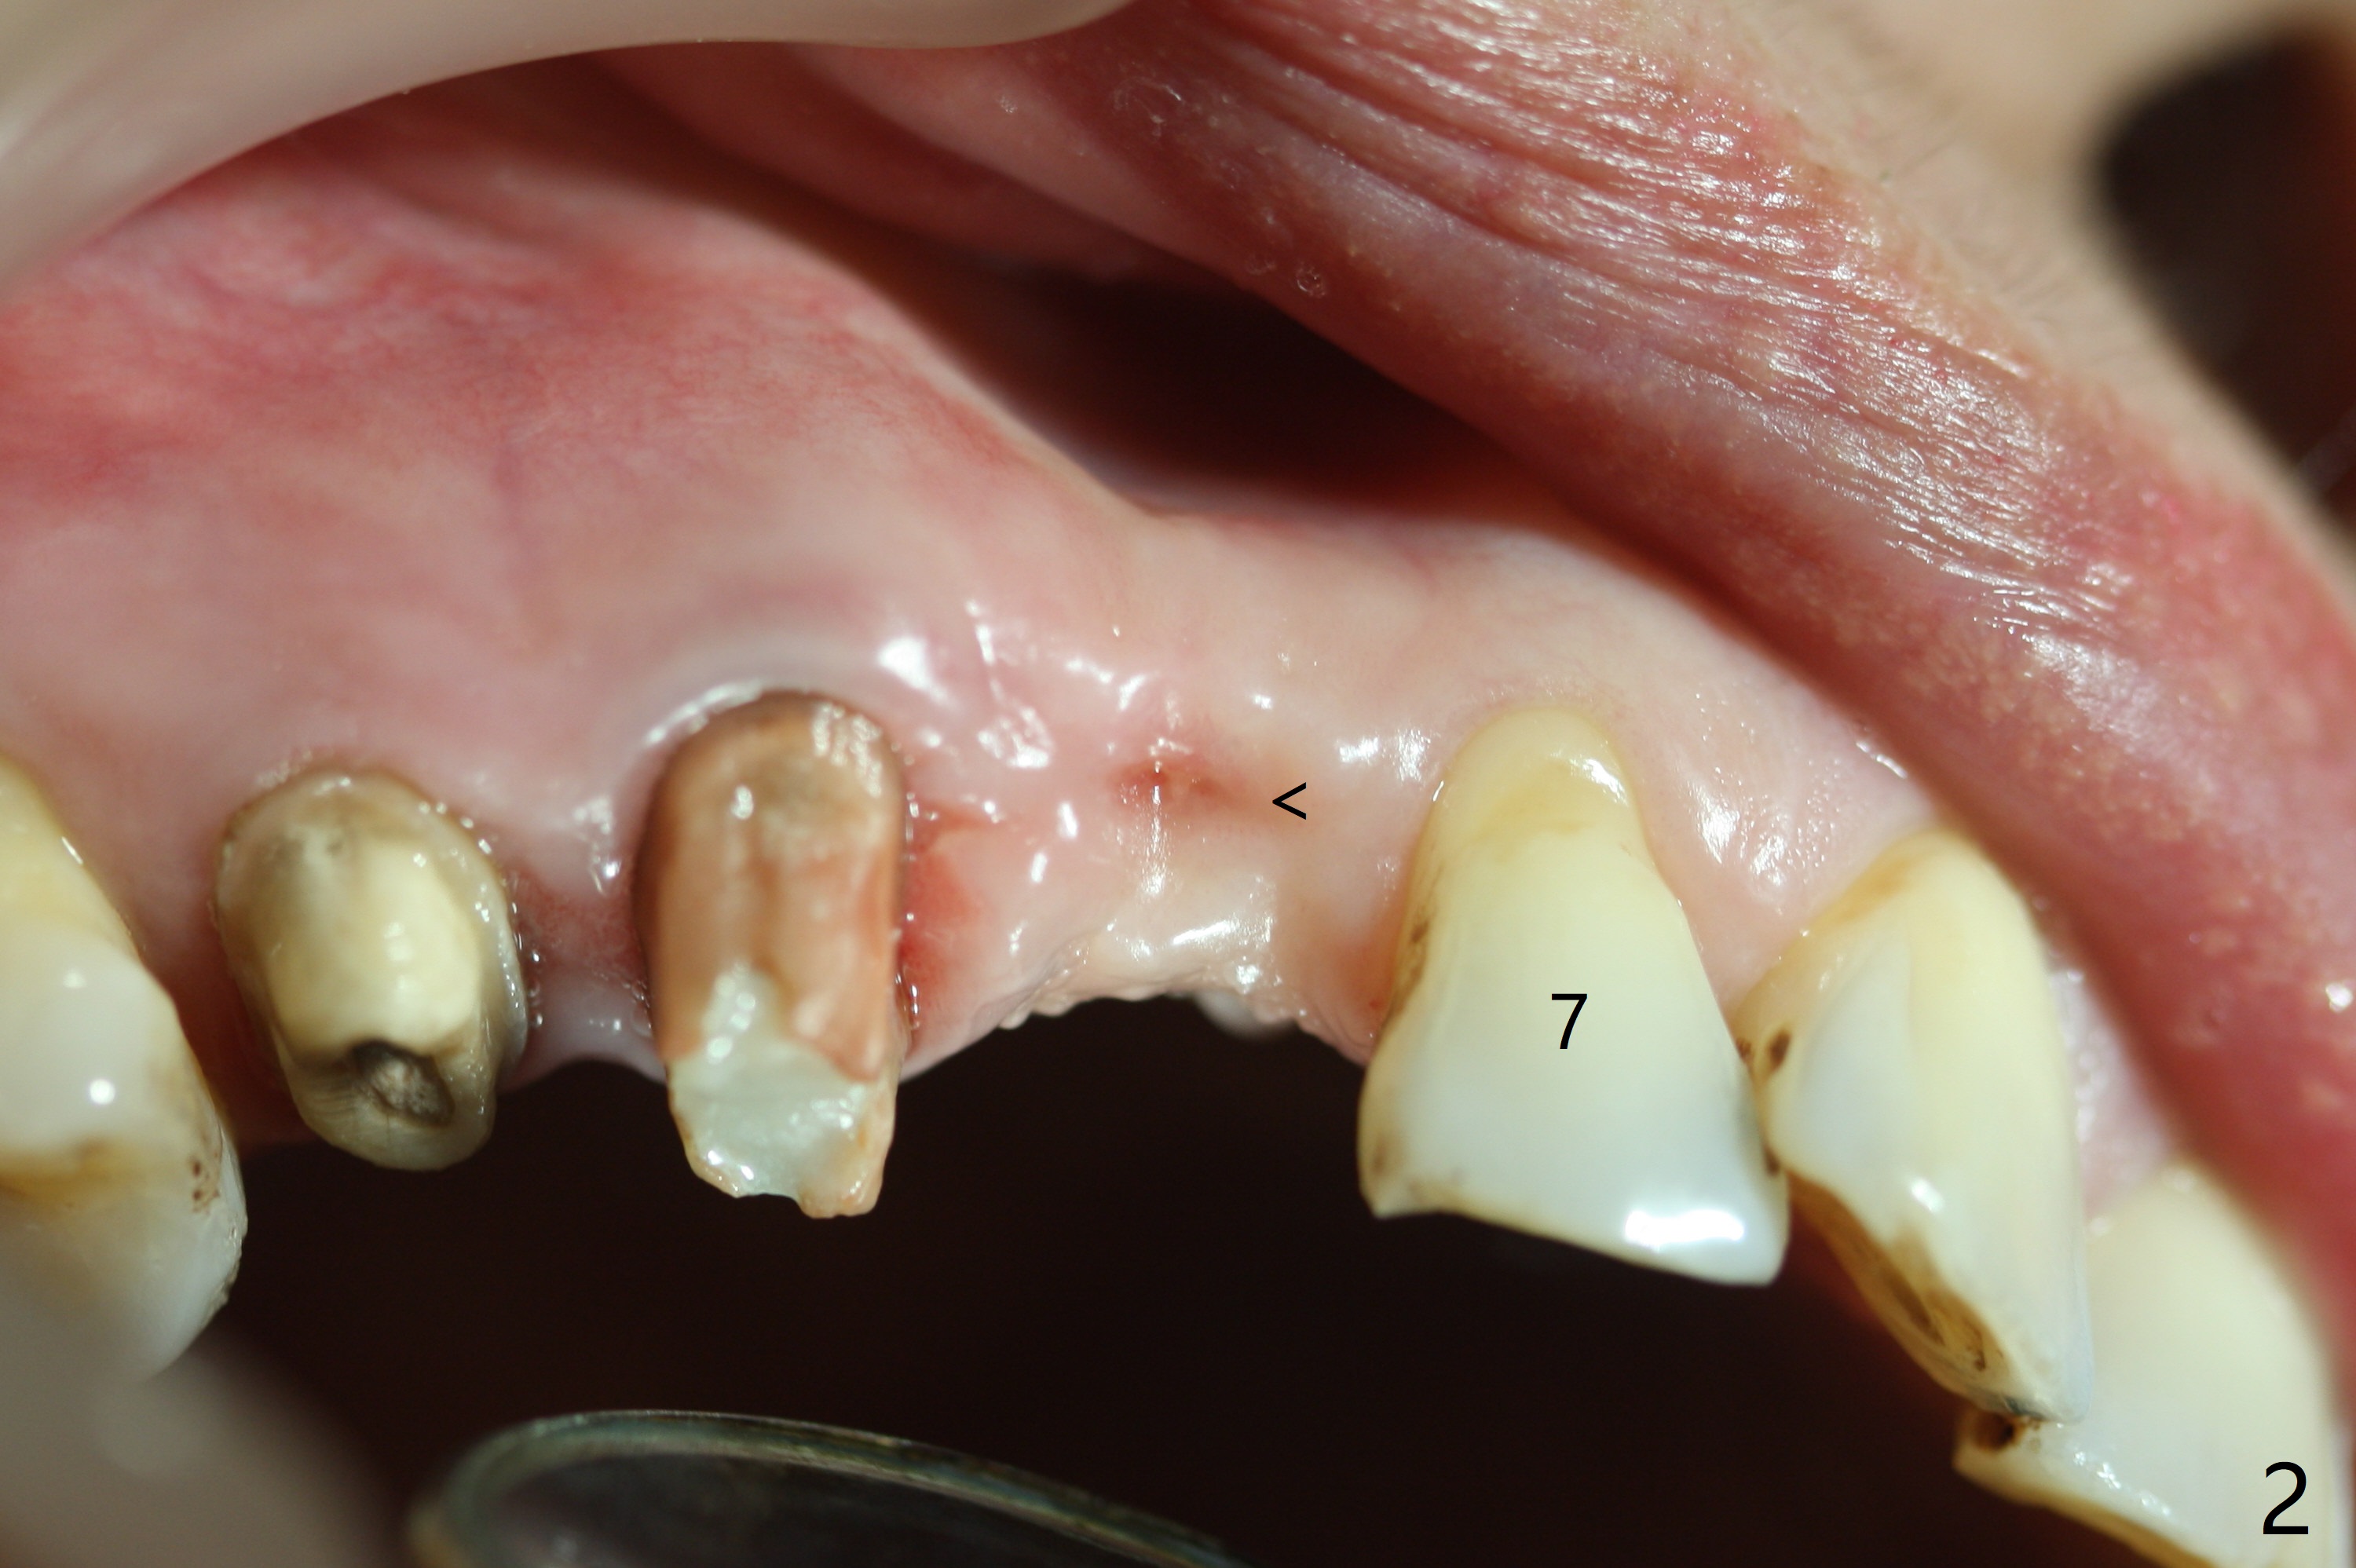

A 60-year-old woman returns for CT 4.5 months post implant removal at #6 (Fig.1). The ridge remains narrow and short because of the impacted tooth. The latter appears necessary to be extracted for a longer implant (12 or 14 mm vs. 10 mm). To accommodate a larger implant (2.5 mm vs. 2.0 mm), prepare DIO bone expander kit. But first, use an initial drill from IS Mini implant kit, followed by a parallel pin for trajectory and occlusal check. Take intraop CBCT if needed. Osteotomy will be initiated palatal (Fig.3 *, as compared to the previous osteotomy (Fig.2 <)). To reduce palatal implant thread exposure, use an implant with 4 mm cuff and place bone graft/collagen membrane. At first take impression with Alginate for wax up. In fact the stent is available. Instead PVS impression is taken for guide. The latter will be used to start initial osteotomy (2.2 mm drill for a few mm (4)), followed by 1.2 mm drill for depth.